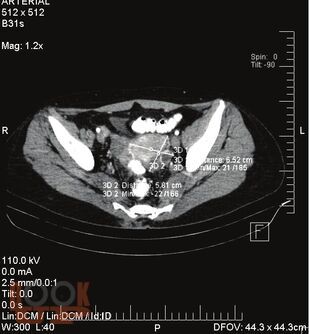

В монографии представлены эпидемиологические аспекты рака шейки матки. Показана роль ВПЧ-инфекции в качестве основного этиологического фактора развития местно-распространенного рака шейки матки, её влияние на показатели общей и безрецидивной выживаемости, особенности метастазирования. Оценено значение вирусной нагрузки и физического статуса вируса ВПЧ в качестве прогностических факторов прогрессирования заболевания. Важная роль отводится современным способам лечения местно-распространенного рака шейки матки. Обсуждается роль химиотерапии в комбинированном лечении больных МРРШМ. Подробно излагаются вопросы, касающиеся особенностей диагностики, лечения и прогноза местнотно-распространенного рака шейки матки у больных пожилого и старческого возрастов. Одним из приоритетных разделов является изучение качества жизни онкогинекологических больных в зависимости от объема проведенного противоопухолевого лечения, обсуждаются психологические и социальные аспекты, приводятся данные о взаимосвязи качества жизни с показателями выживаемости. Анализируется комплекс факторов, в том числе и иммуногистохимические, влияющие на прогноз заболевания. Разрабатываются математические модели прогноза местнораспространенного рака шейки матки.